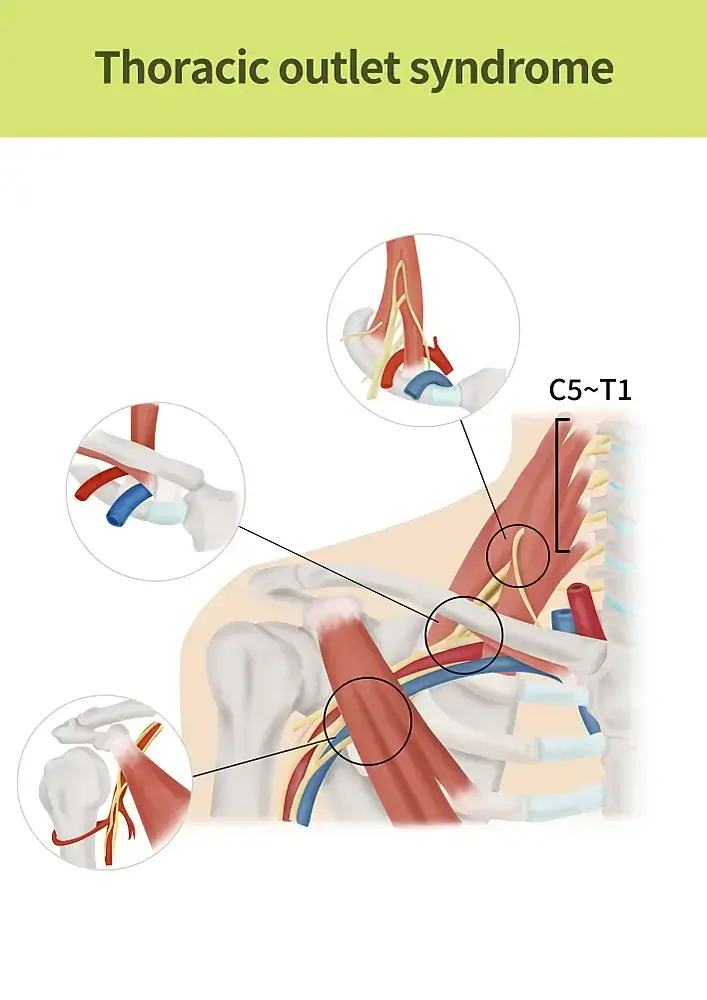

Thoracic Outlet Syndrome

Thoracic Outlet Syndrome (TOS) is a condition characterized by pain or discomfort in the shoulder, neck and arm caused by compression of the nerves, arteries and/or veins in the thoracic outlet. It can cause shortness of breath, fatigue, and chest pain.

The condition is caused by a variety of factors, including obesity, excess weight around the neck and upper back, age, pregnancy, surgery, congenital abnormalities, smoking, tight clothing, and repetitive use of the neck and shoulder muscles.